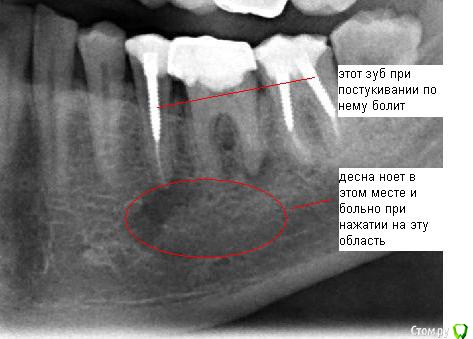

SergeySergey Опубликовано 16 октября, 2015 Поделиться Опубликовано 16 октября, 2015 Киста - что делать ? Заныла десна под 5 и 6 зубом, сделал рентген, результат - киста под 2-мя зубами 5 и 6 и еще киста между корнями у 6-ки.5 зуб болезненно реагирует на постукивания. Хирург и мой постоянный лечащий врач-терапевт говорят - нужно удалять два зуба и кисту, лечить не получится и обосновывают следующим:Проблема что 5 зуб со штифтом и вытащит штифт не возможно, а 6 проблемный в плане перелечивания, так как в канале есть инородное тело (возможно фрагмент инструмента), достать нереально а очаг как раз на верхушке этого корня, передние каналы 6 зуба тоже плохие (не видны), скорее всего не проходимы. Вероятно лечился резорцин-формалиновым методом и очень давно (1995-97 гг) Еще в другом месте врач-терапевт консультировал и говорит - не удалять а лечить все вопросы решаемые - штифт из 5-ки можно извлечь, если не извлечется штифт, то хирург доберется к кисте через челюсть, а 6-ку каналы можно вскрыть. и все вылечить за несколько месяцев и несколько посещений. Ваше мнение ? Что делать идти не к своему врачу а к тому который возьмется или удалять как говорить мой врач и хирург ? Ссылка на комментарий